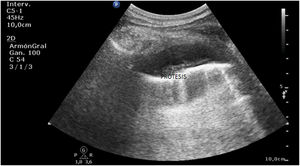

Ingresa en la Unidad de Cuidados Intensivos una paciente por dehiscencia de sutura precoz durante el postoperatorio de una miotomía quirúrgica por divertículo esofágico. Se coloca por vía endoscópica una prótesis metálica autoexpandible en la región dehiscente.

A las pocas horas, en el control sonográfico, se puede apreciar la endoprótesis (fig. 1) con sus pinzas (flechas en la figura 2) en la región del cuerpo gástrico, en la ventana esplenorrenal. A través de una endoscopia se recoloca la prótesis hasta su correcta ubicación. En seguimiento por ecografía, se comprueba la desaparición del dispositivo en el cuerpo del estómago (fig. 3).